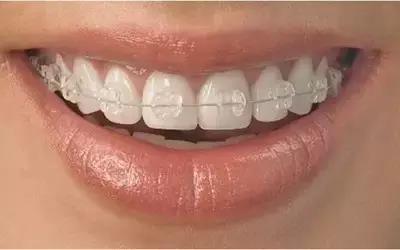

2、半隐形矫治

半隐形矫正即陶瓷托槽牙齿矫治,它使用的托槽近乎透明,粘在牙齿上隐蔽性较好,相对金属牙套更美观。

3、全隐形矫治

全隐形矫治器完全透明,患者可以自行摘戴,较舒适,透明矫治适应症比较严格,要专业医生进行评估。

全隐形矫治(无托槽隐形矫正),其原理是利用高分子塑料弹性膜片对牙齿实现全面的包裹,通过塑料膜片的回弹力对牙齿进行移动。

由于隐形牙套的生产制作融合了3D打印技术等各种高大上技术,它利用电脑分析,精确设计出牙齿移动的过程,这个过程可能分十几到几十步,每步对应一副牙套,通过不断更换牙套使牙齿移动到最终的矫正效果。因为塑料膜片的弹性是有限的,所以每隔7-14天就要更换一副牙套。

西安画美医疗美容医院隐形矫正根据空间、排列、比例、脸型、唇形360°全角度设计,全方位的解决牙齿排列不齐、前突、地包天、龅牙、虎牙等,同时解决颌骨、颅面的不协调,达到面部整体和谐,这种外表近乎透明、舒适感十足、取戴方便、易清洁的隐形矫正完全不影响进食。